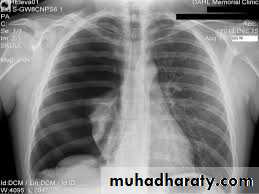

Chest X-rayLower zone shadowing

Decreased lung size

- Bilateral hilar lymphadenopathy , asymptomatic, subside without treatment in about 80-90% of patients

- Pulmonary infiltration and bilateral hilar lymphadenopathy which may cause symptoms such as dyspnoea, cough and fever, but subsides in 40% of patients